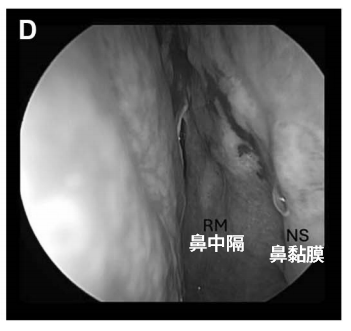

为最大限度降低颅底手术对生活质量的影响,福教授选择单鼻孔入路,结合“筷子”技术配合角度镜及器械操作,该术式在保留鼻腔解剖结构的同时,通过蝶窦颅腔化及鼻咽顶黏膜缝合重建,避免使用鼻中隔黏膜瓣。

与双鼻孔技术不同,该入路在不扩展经鼻通道的情况下即可实现对侧岩斜区的直接抵达。“筷子技术”是核心,将狭小的鼻腔作为内镜和其他器械的“通道”,从而保护了鼻内部的结构,在单鼻孔狭窄的空间内也能获得360°的手术视野,将原本操作空间不足的劣势,转变为提升可操作性的优势。

完整的鼻中隔及蝶窦前壁为内镜与吸引器提供支点,使得在关键神经血管结构附近实现毫米级精准控制。此外,器械与内镜也不会“打架”,手指上极其微小的动作,在吸引器的尖端也能获得所需的移动幅度,从而有利于提高操作的精准度。

术后 4 周内镜复查显示鼻黏膜缝合处愈合良好,无结痂,患者无鼻部不适主诉。